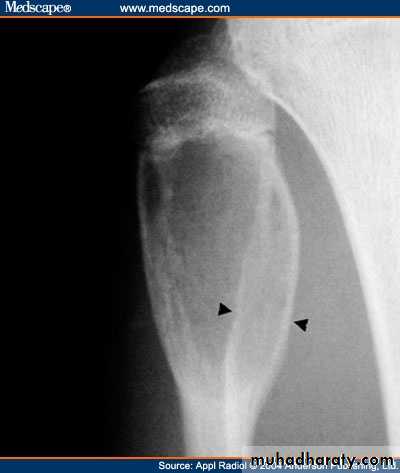

Developmental disorder whereby normal bone is replaced by fibrous tissue with flecks of osteoid.It may affect one bone (monostotic) or multiple bones (polystotic).

The lesion may be very large causes bone expansion and cortical thinning with progressive deformity and sometimes pathological fracture.Lesions occur in metaphysis & diaphysis, proximal femur is a common site it gives characteristic deformity called (shepherd’s-crock deformity(عصا الراعي.

X-ray shows lucent cystic lesion sometimes large and multilocular with bone expansion and cortical thinning it contains multiple calcific spots giving the ground-glass appearance, there is always possible deformity or pathological fracture.